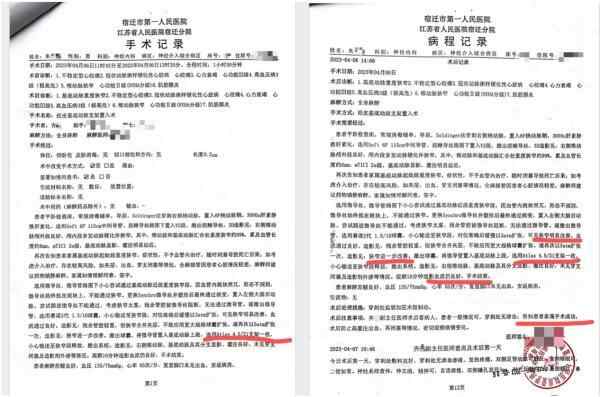

朱先生提供的病程记录和手术记录均显示,手术过程中,齐某选用了一枚Neuroform Atlas 4.5/21支架输送至病变狭窄段释放。病程记录中多次提到血管狭窄问题得到改善,告知家属手术成功。

朱老汉接受经皮基底动脉支架植入术的手术记录及病程记录复印件。朱先生供图根据4月7日至4月10日的查房记录,朱老汉术后病情平稳,症状有所好转。4月10日,朱老汉出院,家属结清了住院医疗费用,合计12万余元,部分自费。

记者注意到,当日收费票据及相关明细中,卫生材料费近10万元,其中,Neuroform Atlas进口颅内支架47000元。

朱老汉的出院收费票据及部分明细。朱先生供图老人突然发病,医生承认支架植入失败5月4日,朱老汉突发严重脑梗。他先被救护车送至江苏省宿迁市泗洪县分金亭医院抢救。